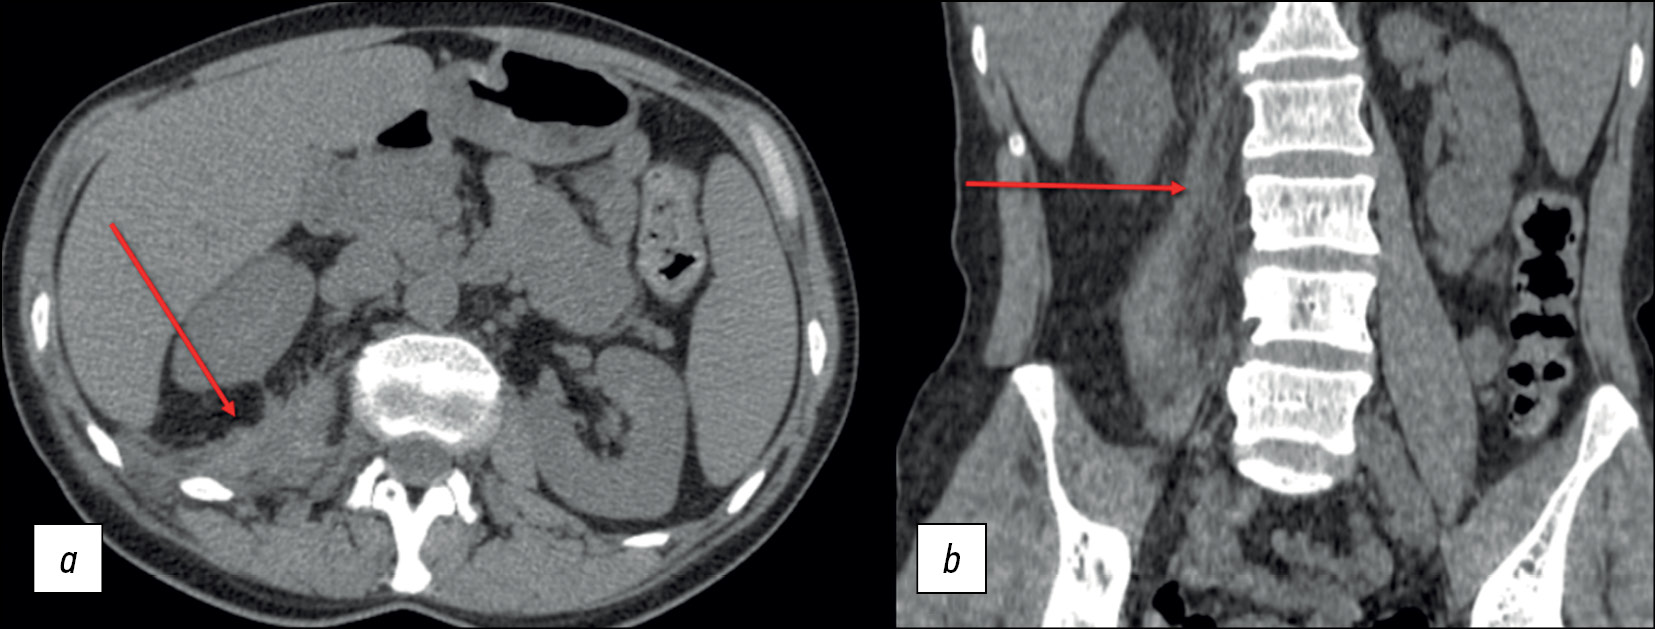

The patient is a 42-year-old female. Back pain and lumbar fistula complaints initially appeared 3 yr ago. According to the medical history, the patient received spinal anesthesia for a cesarean section 6 months prior. The patient experienced fistula relapses approximately three to five times a year. At the presentation, a magnetic resonance imaging (MRI) revealed bony and fibrous ankylosis ТhVII–ТhVIII (Figure 1), which could indicate both spondylitis in remission and contact spinal infection.

Fig. 1. Thoracic spine MRI: (а) STIR mode, sagittal plane; (b) T1WI mode, sagittal plane; and (c) T1WI mode, coronal plane. The arrows indicate bony and fibrous ankylosis ТhVII–ТhVIII.